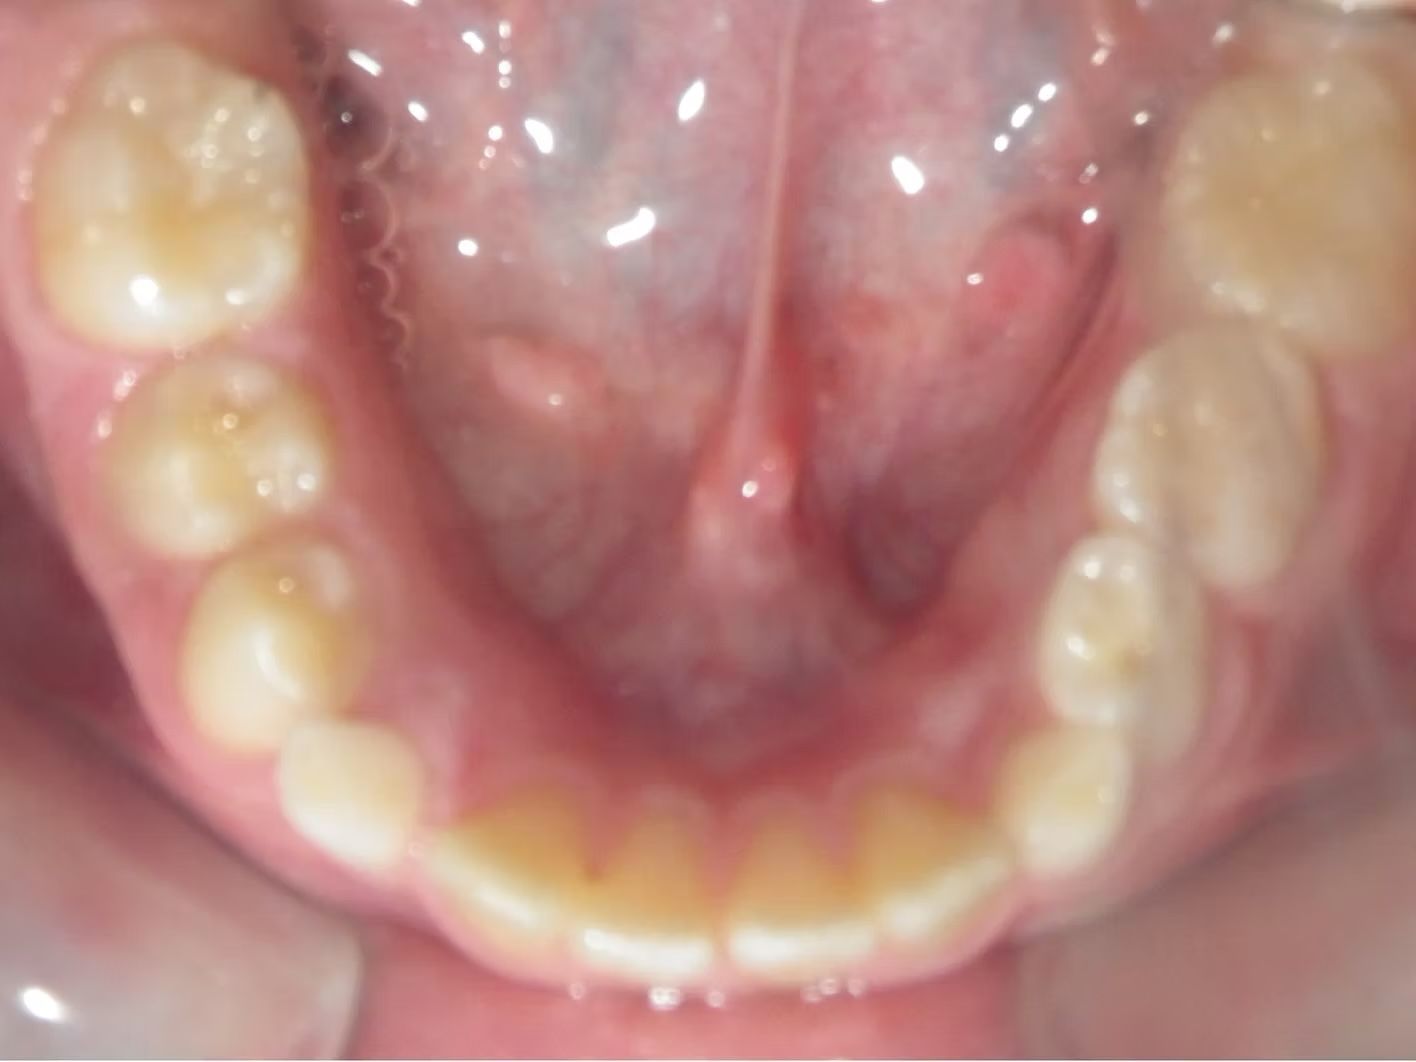

Imset

Imset came to see Dr. Bret because he felt like the upper and lower teeth were too crowded. The lower canines were in cross-bite with the upper teeth and there was significant crowding in the lower arch. He previously had 2 teeth pulled in the top and at the time none in the bottom. This made the top jaw smaller than the lower and the lower teeth didn't have room to fit inside the top teeth. We had 2 lower teeth extracted, and then aligned the upper and lower teeth to fit excellently together- no more crowding!